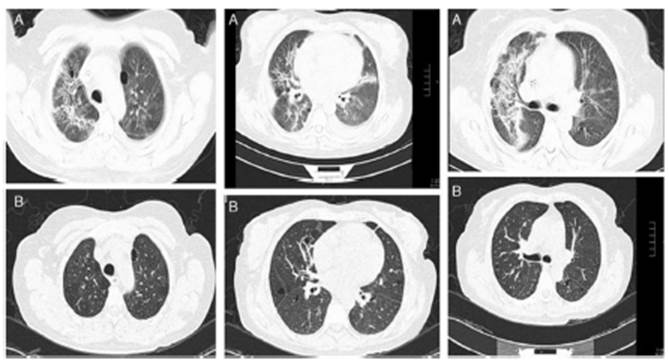

The inflammation at the pulmonary level correlates with the ground-glass image on high-resolution chest tomography (HRCT) and may improve with glucocorticoids. (29 Our working group described that patient with RA-ILD treated with glucocorticoids at a maximum daily dose of 50 mg prednisone/day, together with DMARDs, (29 can improve in observed forced vital capacity (FVC) at six months after initiation of treatment, with up to 15% absolute difference. This improvement correlates with decreased ground glass and consolidations observed on HRCT29 (Fig. 2). However, this improvement is not observed in fibrosing patterns; on the contrary, patients with RA-ILD with usual interstitial pneumonia (UIP) or fibrotic nonspecific interstitial pneumonia (NSIP) patterns may have a behavior of ILD, such as progressive pulmonary fibrosis (PPF). (2,30

Fig. 2 (A) Baseline HRCT of a patient with RA-ILD, showing perivascular and randomly distributed cysts, with ground-glass opacities and areas of pulmonary consolidation with bronchocentric thickening of the interstitium. (B) HRCT one year after starting treatment with prednisone and methotrexate. A significant decrease in ground glass, resolution of the consolidation areas and bronchocentric thickening of the pulmonary interstitium. Image from Rojas-Serrano J, González-Velásquez E, Mejía M, Sánchez-Rodríguez A, Carrillo G. Interstitial lung disease related to rheumatoid arthritis: evolution after treatment. Reumatologia Clinica. 2012;8:68-71.

In practice, it is advisable to discuss with the imaging expert the degree of extension of the findings on HRCT compatible with inflammation and decide on treatment with glucocorticoid based on that. If the extension is greater than 20% according to the Goh scale, there is no doubt that prednisone with a maximum dose of 50 mg/day may benefit the patient. In case of a lesser extent, a dose between 20 to 50 mg of prednisone per day should be decided on a case-by-case basis. Generally, the initial dose is maintained for 4-6 weeks, and then a gradual decrease of the glucocorticoid dose is initiated. In office visits and daily consultations, a frequent comment that one of the authors (JRS) makes to the medical team is that he has never regretted prescribing or increasing the prednisone dose in a patient with RA-ILD. Still, he has occasionally questioned whether to decrease or discontinue the dose. Recently, a literature citation that justify that comment was published. Changetal. (13 reported that glucocorticoid use is strongly associated with protection against lung disease progression and/or death (RR: 0.28, 95% CI: 0.09-0.81). One explanation is that despite the adverse effects associated with glucocorticoid therapy, judicious use of glucocorticoids in a patient with RA-ILD contributes to tighter control of RA activity, reflected in the decreased inflammatory process in the lungs.